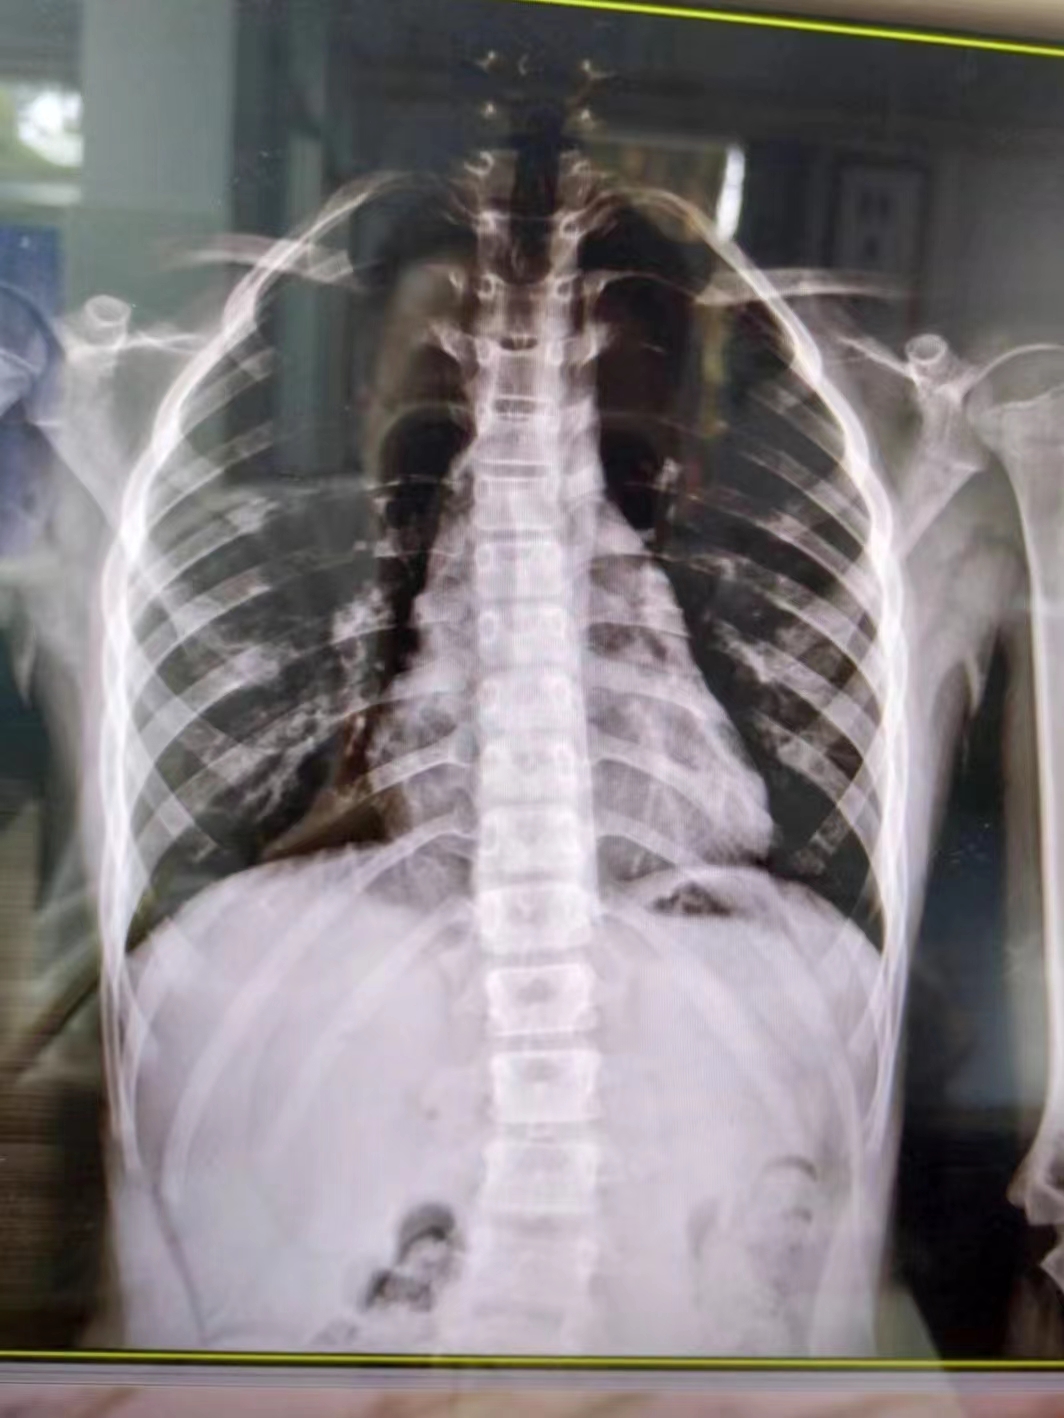

在康復(fù)醫(yī)學(xué)科,徐棟醫(yī)生通過(guò)X線片確認(rèn)小朋友患有脊柱側(cè)彎,“其實(shí)肉眼也可以看到小朋友的脊柱有彎曲弧度,家長(zhǎng)的擔(dān)心是正確的。”

幸運(yùn)的是,由于媽媽發(fā)現(xiàn)及時(shí),小朋友的情況無(wú)需手術(shù)治療,經(jīng)過(guò)7次整脊手法按摩治療后,側(cè)彎明顯好轉(zhuǎn)。